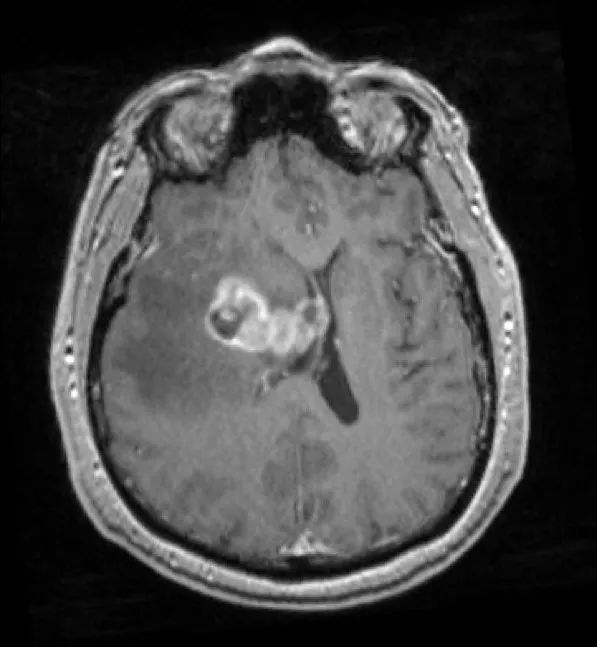

患者为55岁男性,因“跌倒频率增加和左侧肢体无力1周余”就诊。 3年前患者曾于外院行肺癌切除术,但患者后来失访,且无法明确癌变性质和分期。 入院时神经系统查体无异常。 外院头颅CT见颅内出血灶,胸腹盆腔CT未见异常。 立体定向颅内病变活检提示肿瘤为低分化转移癌,细胞标志物检测考虑鳞状细胞癌。

立体定向导航下行右额开颅。 鉴于肿瘤位置深,计划在60mm长BrainPath(厂家NICO)管型牵开器辅助下以微侵袭方式切除该肿瘤。 术前借助导航系统于右侧额叶寻找对应肿瘤长轴的脑沟并以此为进入点确定术中路径,手术通道与肿瘤长轴平行可以有效降低纤维传导束和基底节的损伤风险。

右额开颅最重要的注意事项就是骨瓣应该位于冠状缝前方以防误伤中央前回。 如果患者为左利手,应避开额下回,尤其三角部和盖部,以免损伤Broca区。 肿瘤尾端侵犯尾状核、内囊前肢和侧脑室额角,部分肿瘤已经毗邻室间孔,因此可能与穹窿、丘纹静脉和尾状核静脉关系密切。

术后患者安返神经ICU。 术后使用地塞米松并于1周内迅速减量撤药。 使用左乙拉西坦500mg bid预防性抗癫痫。 术后第1天复查MRI见肿瘤近全切。